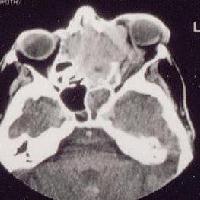

This 72 year-old woman was referred by her family doctor because of a left proptosis with orbital pain of five week duration. A CT scan was performed and shown as above.a. What is the diagnosis?